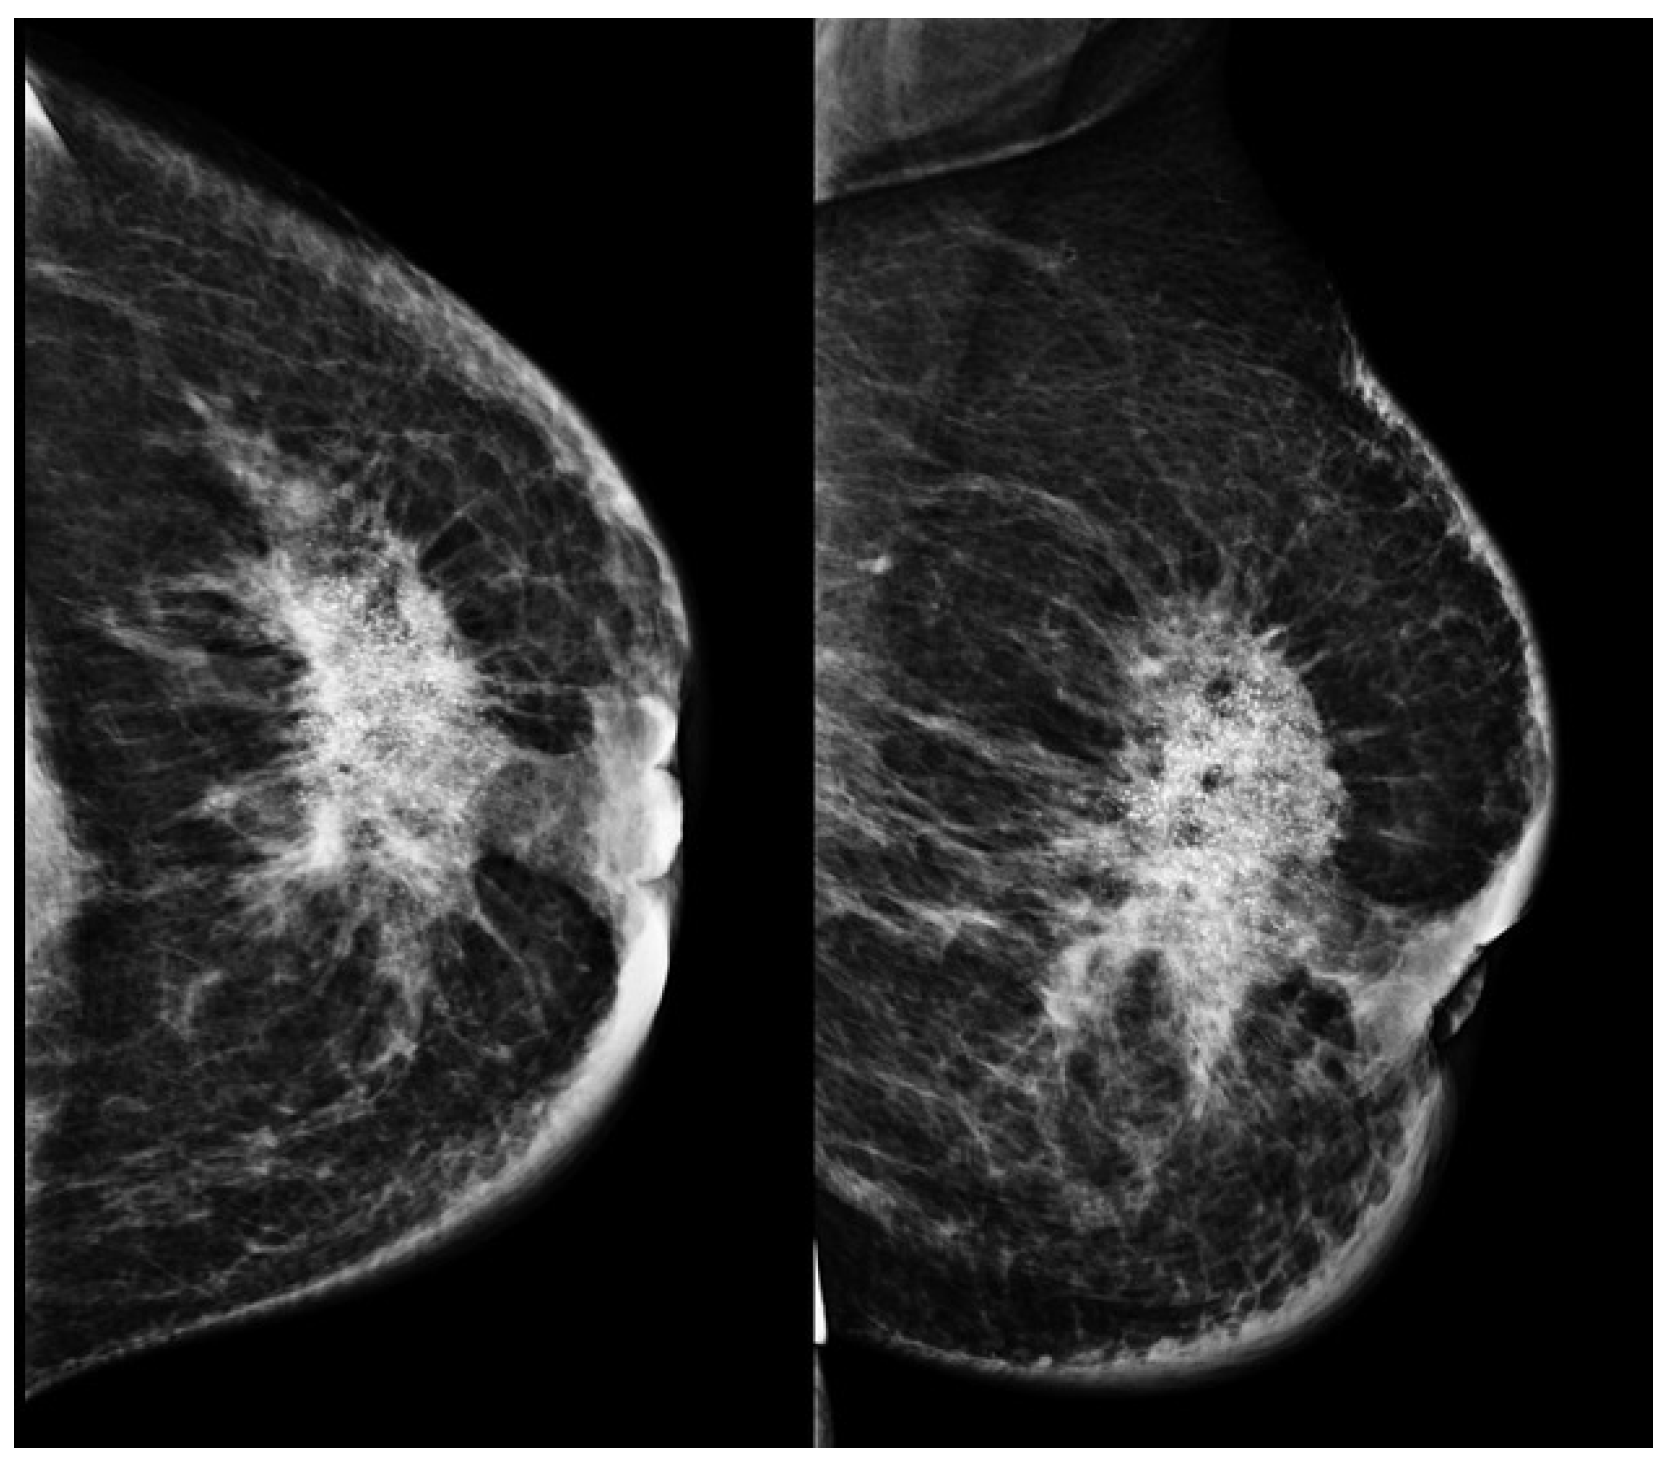

2.3. Mammography

- Sickles, E. Mammographic features of “early” breast cancer. Am. J. Roentgenol. 1984, 143, 461–464. [Google Scholar] [CrossRef]

- Gajdos, C.; Tartter, P.I.; Bleiweiss, I.J.; Hermann, G.; De Csepel, J.; Estabrook, A.; Rademaker, A.W. Mammographic appearance of nonpalpable breast cancer reflects pathologic characteristics. Ann. Surg. 2002, 235, 246–251. [Google Scholar] [CrossRef] [PubMed]

- Leibman, A.J.; Lewis, M.; Kruse, B. Tubular carcinoma of the breast: Mammographic appearance. Am. J. Roentgenol. 1993, 160, 263–265. [Google Scholar] [CrossRef][Green Version]

- Sturesdotter, L.; Sandsveden, M.; Johnson, K.; Larsson, A.M.; Zackrisson, S.; Sartor, H. Mammographic tumour appearance is related to clinicopathological factors and surrogate molecular breast cancer subtype. Sci. Rep. 2020, 10, 20814. [Google Scholar] [CrossRef]